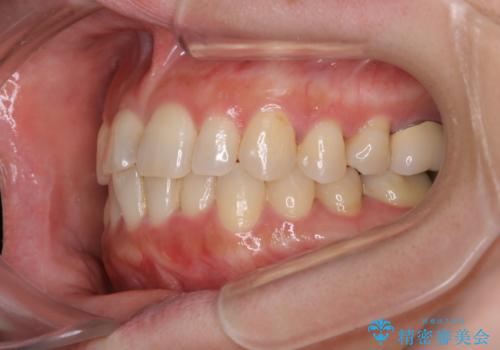

- 前歯のがたつきと反対咬合を主訴に来院されました。

インビザライン・クリンチェック(歯のシミュレーション)を行い、

インビザラインライトで治せる範囲であることを確認し治療を開始することになりました。

今回はクリンチェックを作成したのちに、枚数が少なくても可能であることが判明したためインビザラインライトでの治療を行いました。